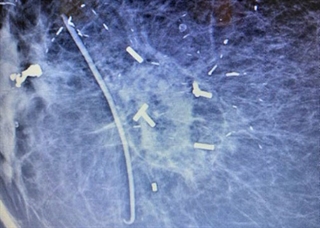

After a biopsy or tumor removal, the Accusyte fiducial sutures are sewn around the perimeter of the tumor bed at the anterior, posterior, middle, and lateral planes of the tumor cavity. The fiducials allow for accurate delineation of target volumes during treatment planning and assist with image guided radiation therapy (IGRT) before each session.

The fiducial markers are woven within an absorbable suture. When the body absorbs the suture, the fiducial markers remain within the tissue. Migration of the markers from their original position is unlikely, as the tissue produced during the healing process holds the markers in place. Sutures are sewn into place using the same technique as other sutures commonly used.

Accusyte 3-D Fiducial Marker Suture Set, 1 x 4 mm marker embedded into each suture. One box contains 6 sutures. One box per patient.